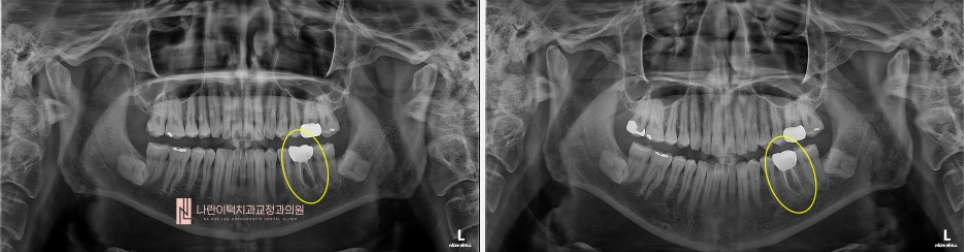

초진 파노라마 엑스레이 사진 Panorama X-ray

1년전 신경치료하고 씌운 좌측 하악 어금니 (#36)의 저작시 통증을 주소로 본원에 내원 하셨습니다.

좌측 하악 첫번째 어금니(#36)의 두 다리 사이에 검은 음영(염증)이 보입니다.(빨간 화살표)

치아 내부에 파절 물질?처럼 의심되는 부위도 존재하네요. (노란 화살표)

신경치료전문의의 눈에는 찾지 못한 신경관(뿌리) 하나가 매직아이처럼 보입니다.

(초록 실선 + 노란 점선) 이 신경관 하나를 찾아서 잘 마무리 해주면 뿌리끝염증이 낫을 것 같습니다!